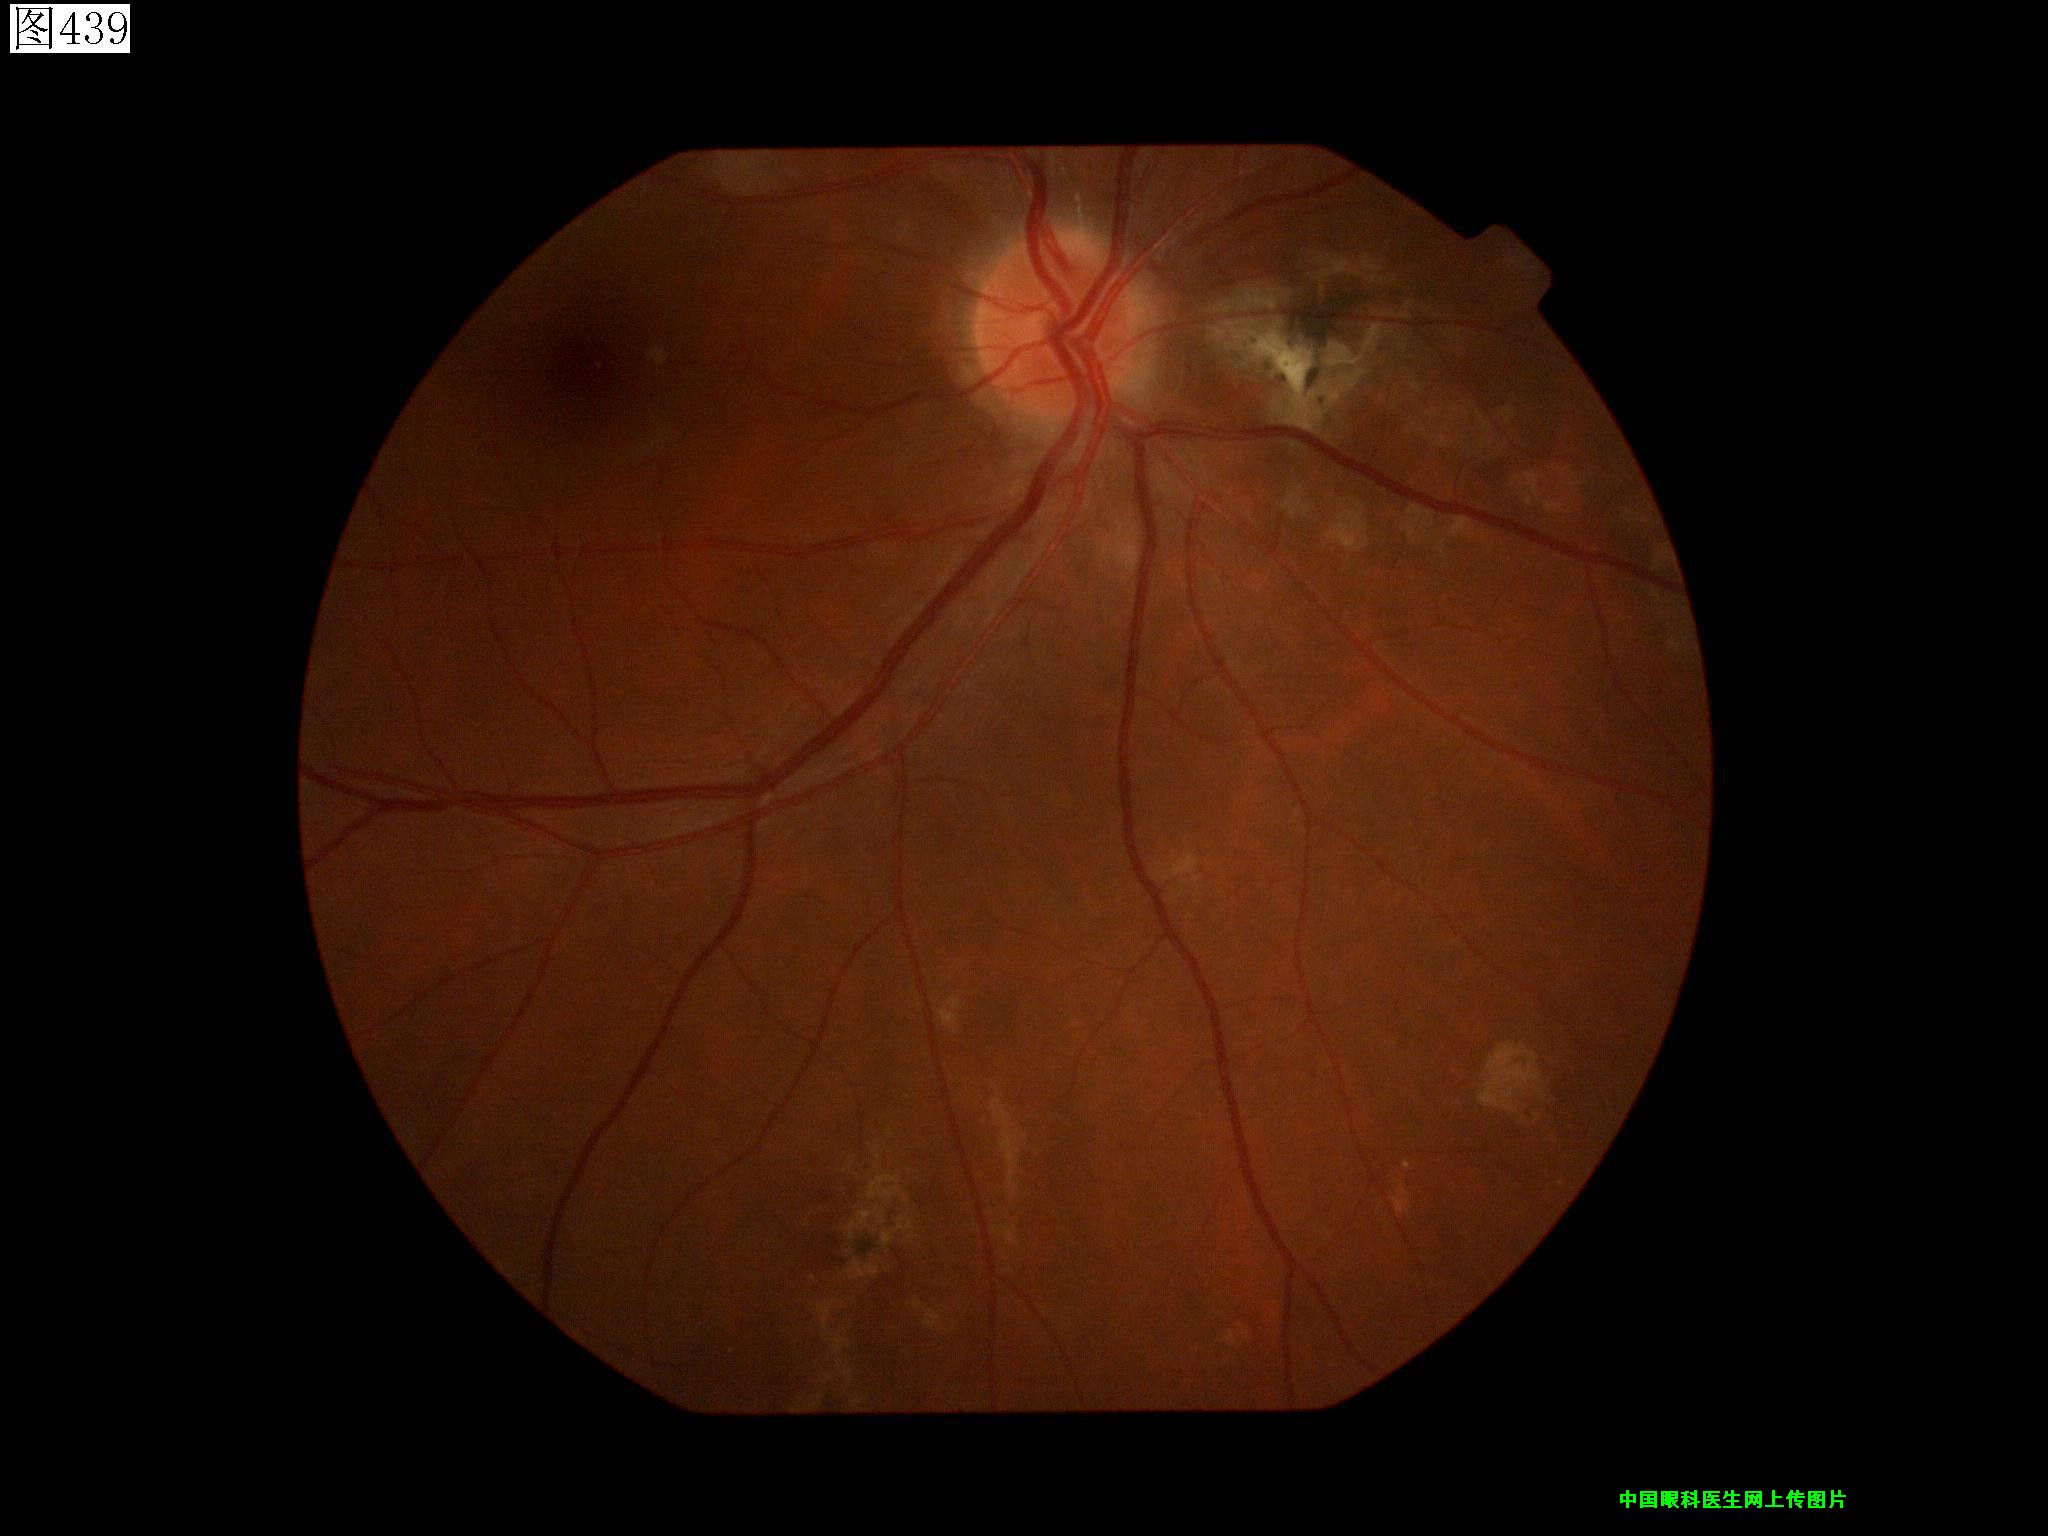

437 438 439 440